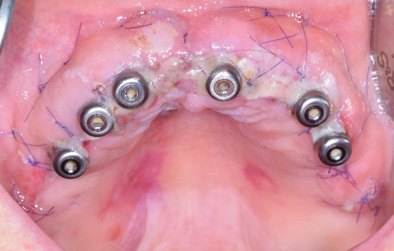

La patiente a été adressée au cabinet par son dentiste traitant pour une solution de remplacement de son bridge maxillaire en fin de vie. Une solution implantaire lui a été proposée pour la réhabilitation de sa mâchoire soit les extractions des dents, mise en place des implants avec aménagement osseux, le tout lors de la même intervention sous sédation vigile. Un Bridge fixe implantaire provisoire et esthétique a été placé 48 heures après l’intervention. Cette prothèse restera en bouche au moins 6 mois pour valider les implants, l’esthétique et la fonction avant de passer aux empreintes pour la prothèse finale (bridge céramique) qui sera totalement adaptée et personnalisée à la demande de la patiente.